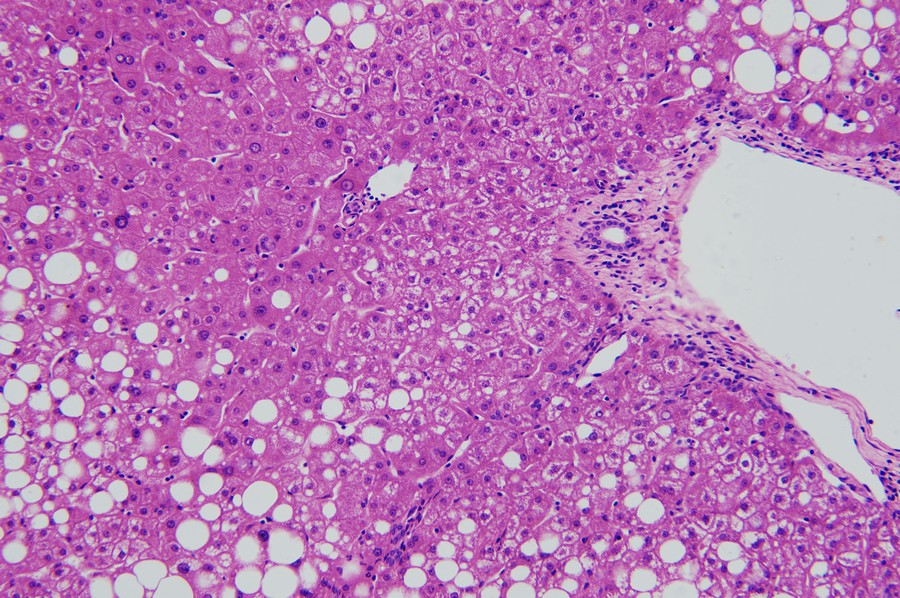

ML31下的脂肪肝:小空泡

當肝細胞出現(xiàn)脂肪變性,鏡下可見細胞內(nèi)出現(xiàn)大小不一空泡,早期主要在細胞核周圍形成小空泡。

ML31下的脂肪肝:大空泡

隨著情況加重,空泡會增多合并形成大空泡,空泡占比越高,脂肪肝情況越嚴重。

ML31下的脂肪肝:肝細胞氣球樣變

在這個視野中我們還可以看到肝細胞的氣球樣變,顯示肝細胞受損進展中。當肝細胞受損后,水分增多會引起肝細胞脹大、胞漿疏松化,進一步發(fā)展肝細胞脹大如球形,胞漿幾乎透明,這就是肝細胞的氣球樣變。